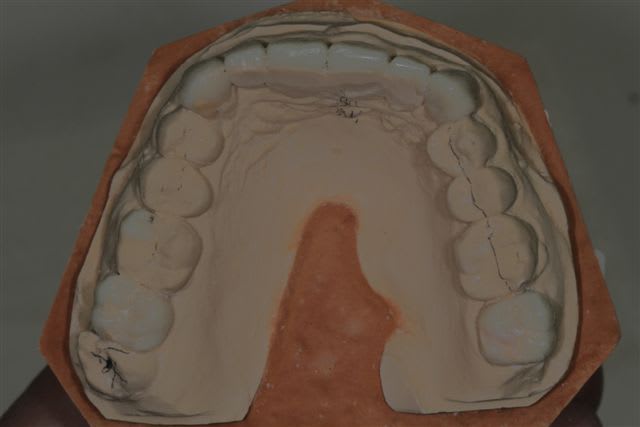

Il semble évident que ceci ne peut être traité que de façon globale, mais la difficulté est de le faire comprendre à la patiente, qui veut seulement un "sourire".

Donc dans un premier temps pano, pour bilan et empreintes pour essayer de lui faire comprendre l'étendue du problème.

premier wax up à minima

Mais autant un wax up ça nous parles, autant la patiente ne déclenche pas, et commence à douter.